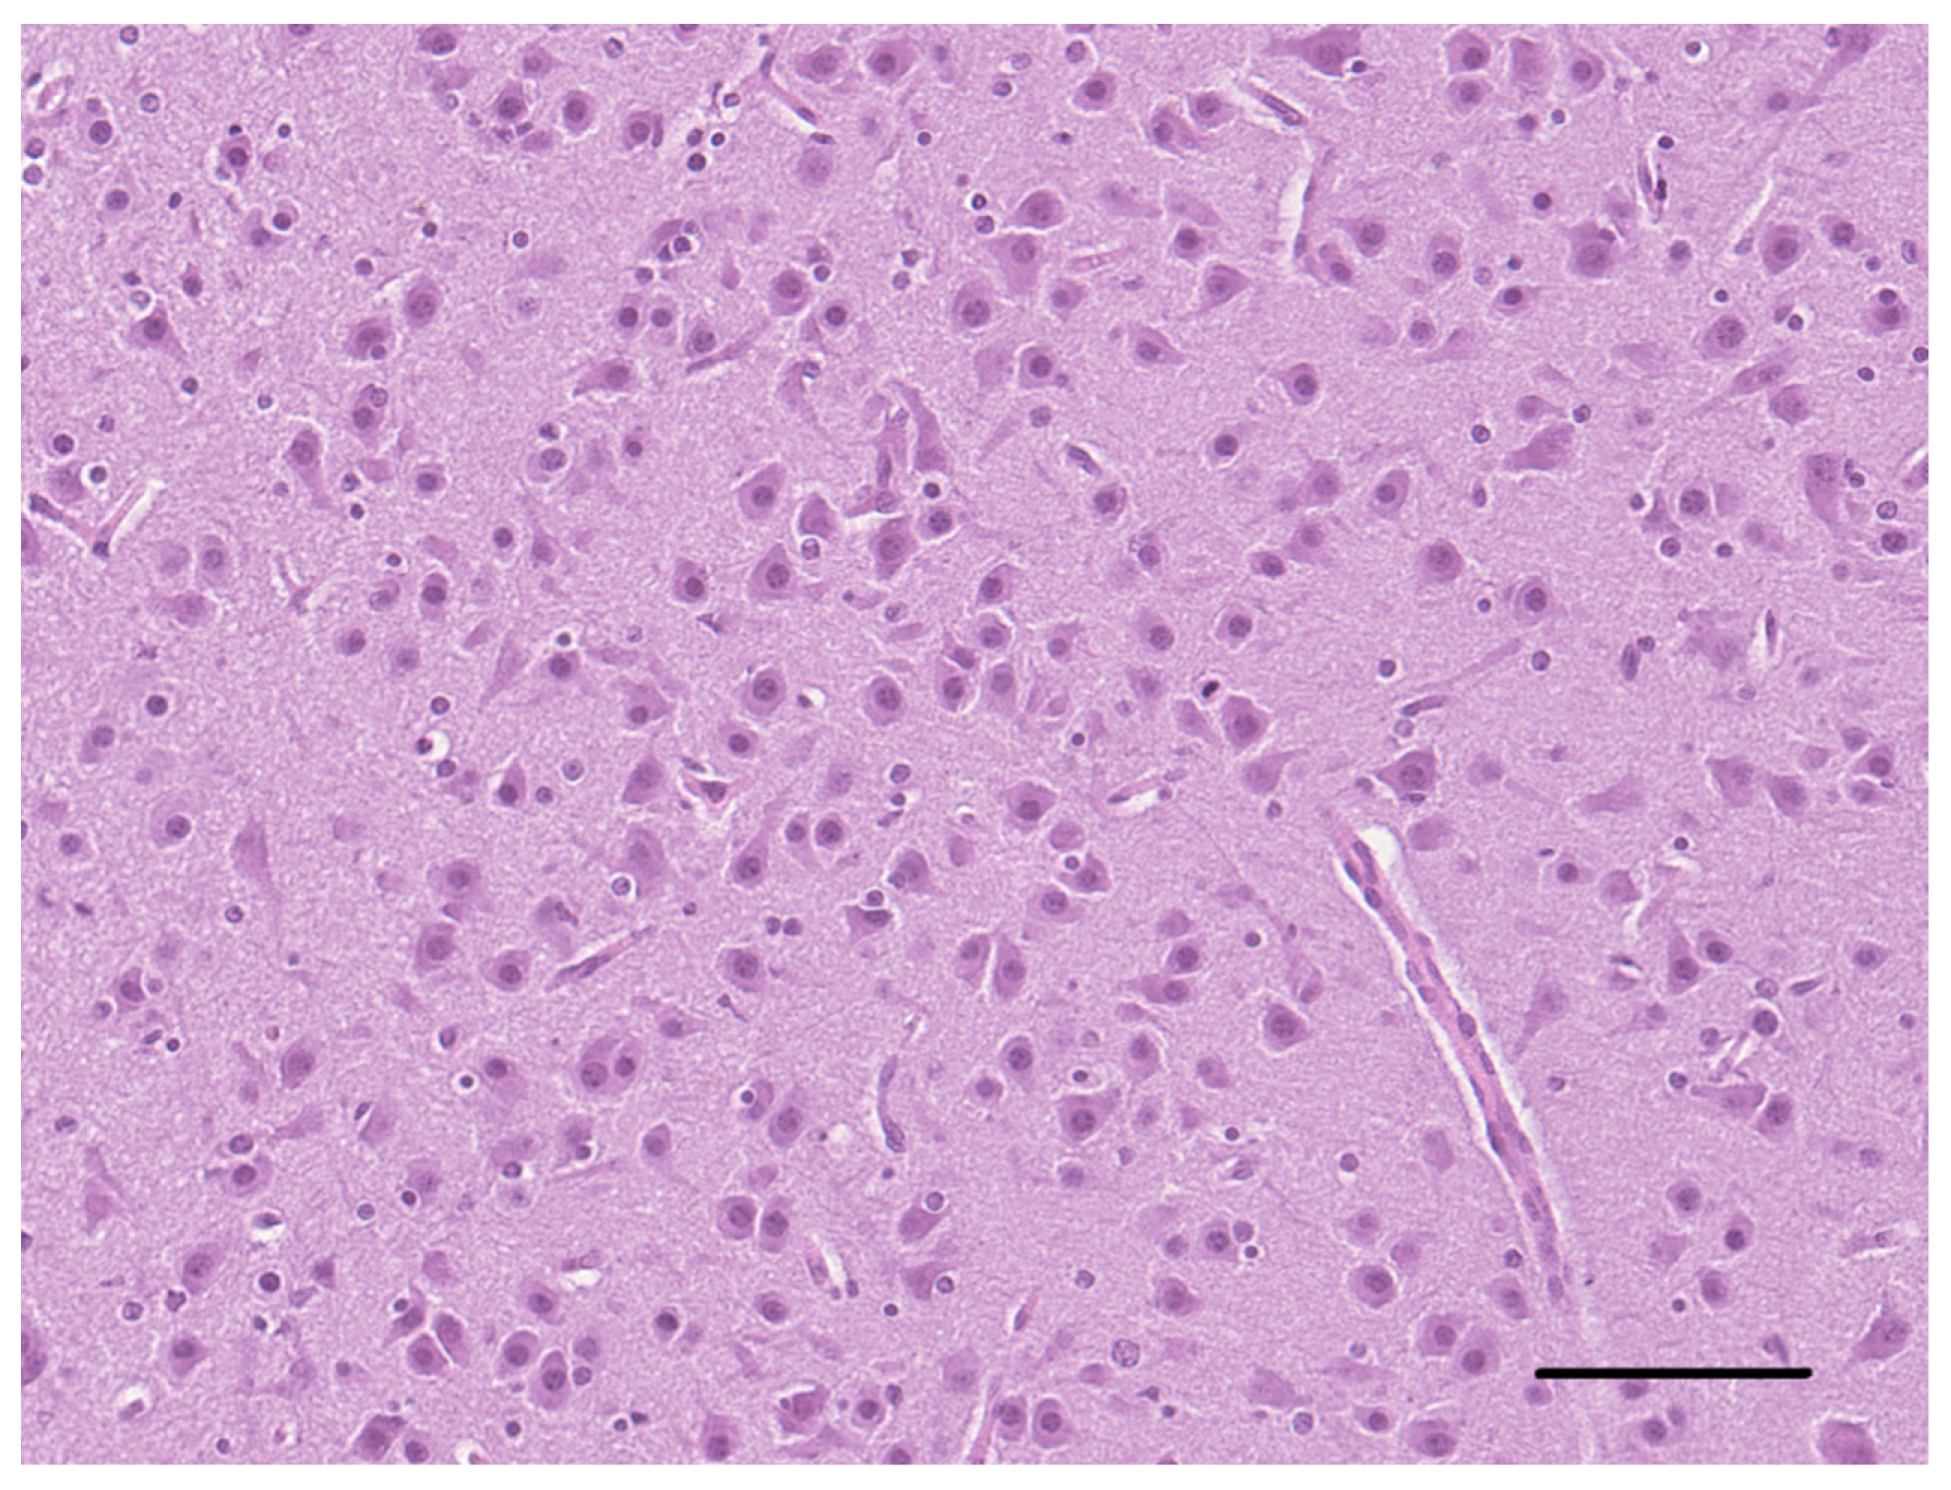

2. Case Description